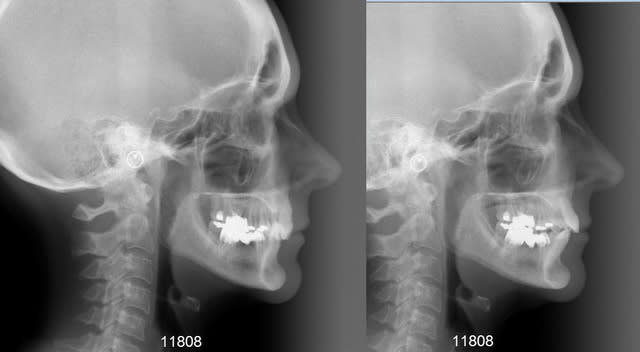

11808 t l  avant apr s astyjo - Eugenol

11808 t l 2 avant apr s coywhl - Eugenol

Je pense qd même que sur la télé de profil final, la zone apicale des incisives est floue sur le plan osseux...

Et que de tte les façons le mur osseux vestibulaire est si fin que la pérénité est très très loin d être assurée mais ce n est que l avis de Pp :-)))))))))))))